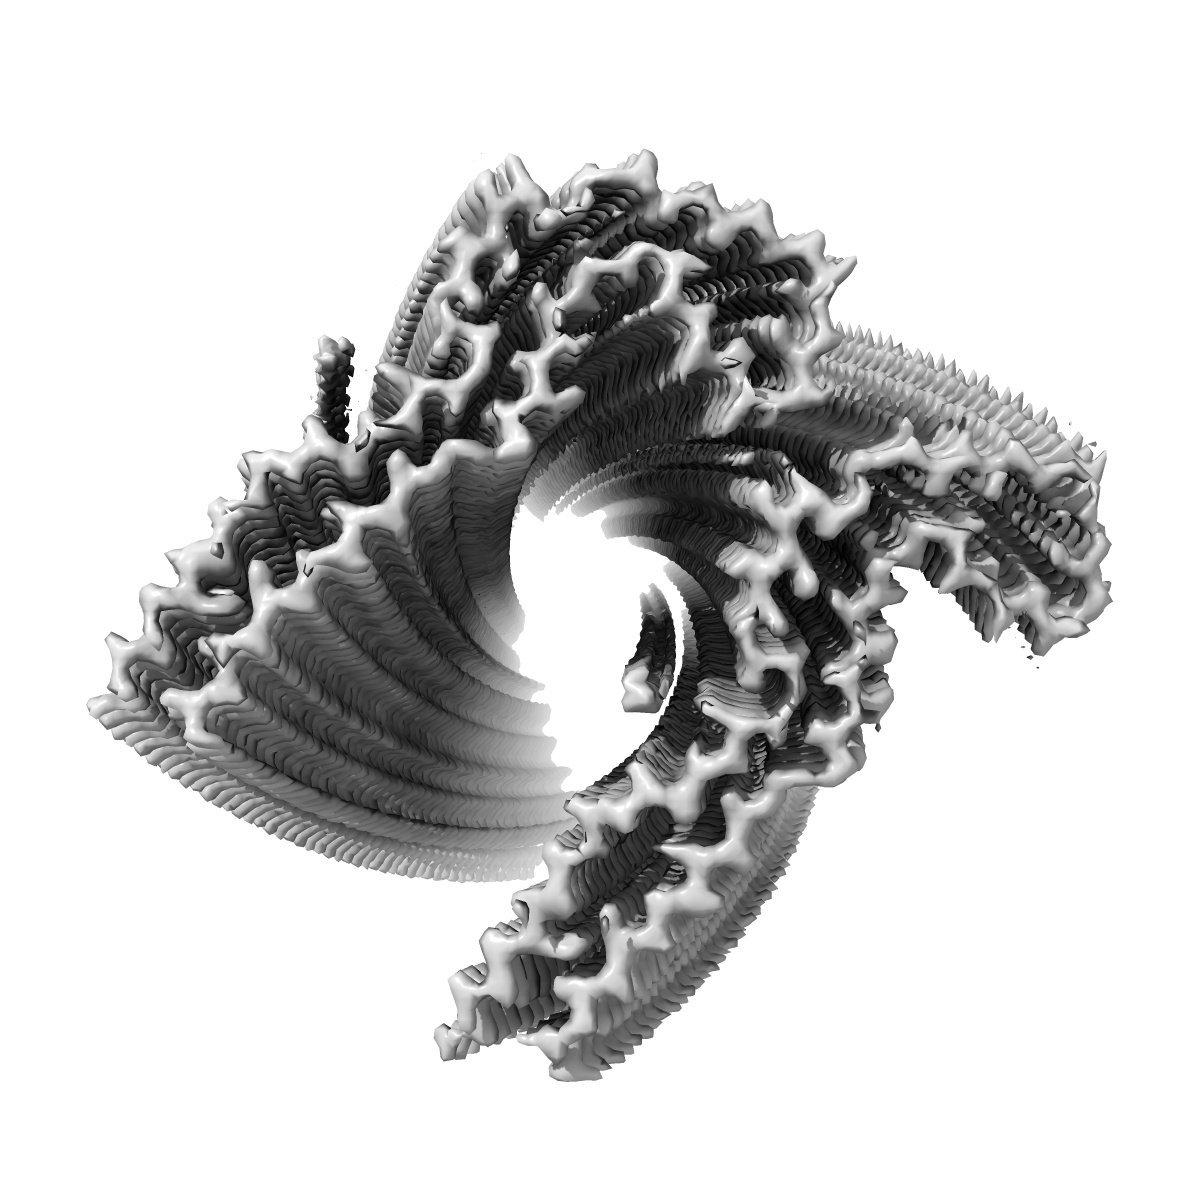

In vitro assembled 300-391 tau filaments in PBS (36a)

EMD-14029

Helical reconstruction

2.61 Å

Sample Organism: Homo sapiens

Sample: Tau

Fitted models: 7qk2

Deposition Authors: Lovestam S, Scheres SHW

Assembly of recombinant tau into filaments identical to those of Alzheimer's disease and chronic traumatic encephalopathy.

Lovestam S, Koh FA, van Knippenberg B , Kotecha A , Murzin AG, Goedert M , Scheres SHW

(2022) eLife , 11